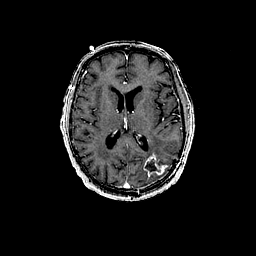

Glioma overlay -- Slice #65

[Home][Help][Clinical] Slice 65